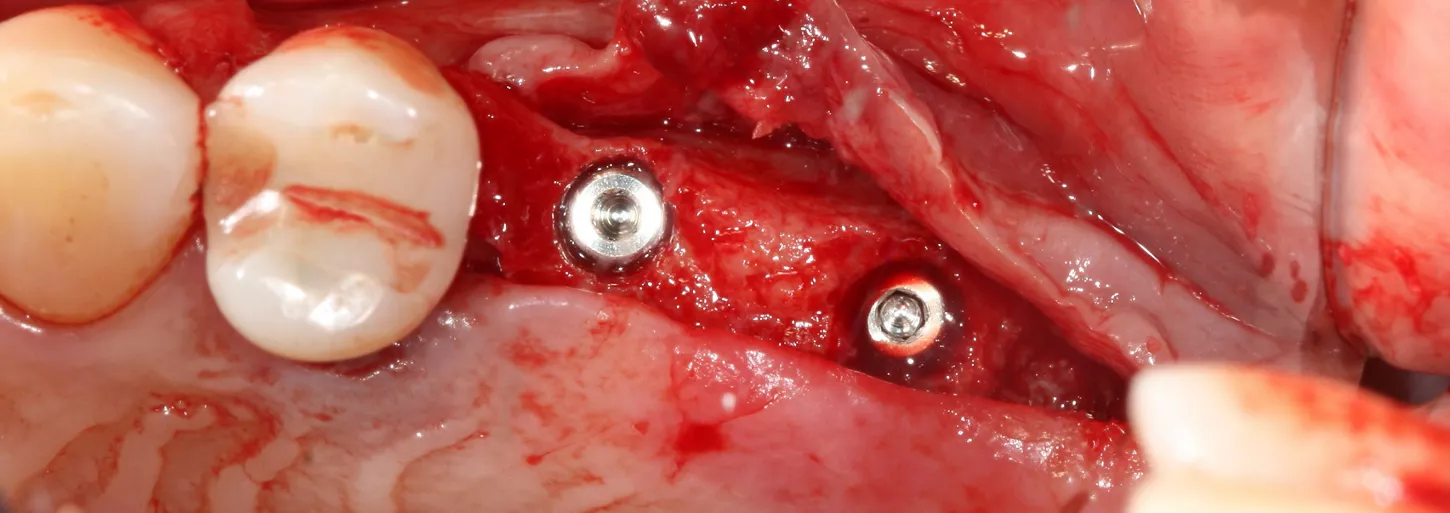

12a-b-c. The design of the Axiom X3® ensures atraumatic implant placement with the micro motor. The Axiom X3® also preserves bone, even if the ridge is thin and resorbed. Despite the meager quantity of vestibular cortical bone, there was no perforation or rupture of the crestal margin.

13. The implants were placed 0.5–1 mm subcrestally. Note the thinness of the vestibular cortical bone at the 25 implant on this occlusal view. Despite this, we achieved perfectly acceptable stability values of 19 and 20 Ncm.